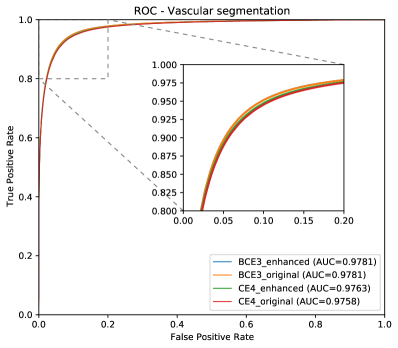

As commented in the previous sections, we include three ROC and PR curves, one for each structure of interest: arteries (A), veins (V), and Vascular Tree (VT)—that is, vessels—. Figure 9 depicts the ROC and PR curves for the different networks in the DRIVE-test set.

Additionally, all AUC values of the curves are summarized in Table 2.

As it can be observed in the vasculature segmentation results of Figures 8 and 9 as well as Table 2, the best performance is achieved by the proposed MS approach using the BCE3 loss, either using the enhanced or the original retinography as input, and regardless of the target class. For each structure of interest, i.e. arteries, veins and vessels, both the AUC-ROC and AUC-PR values are higher with the MS approach than with the traditional CE4 one. Furthermore, AUC-PR and AUC-ROC for vessels are significantly higher for the MS approach than for CE4 (), as well as other statistics like AUC-ROC for arteries () and AUC-ROC por veins ().